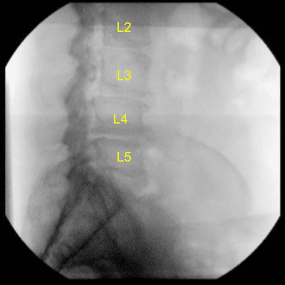

Intraoperative X-ray

AP and lateral radiographs were used to position him in a true lateral and AP position with his spinous processes equidistant from the pedicles and with his residual endplates crisp on lateral fluoroscopy. The left flank position was then carefully scrubbed, prepped and draped after two separate transverse flank incisions were marked out overlying the L3-L4 and L4-L5 disc spaces under fluoroscopy.